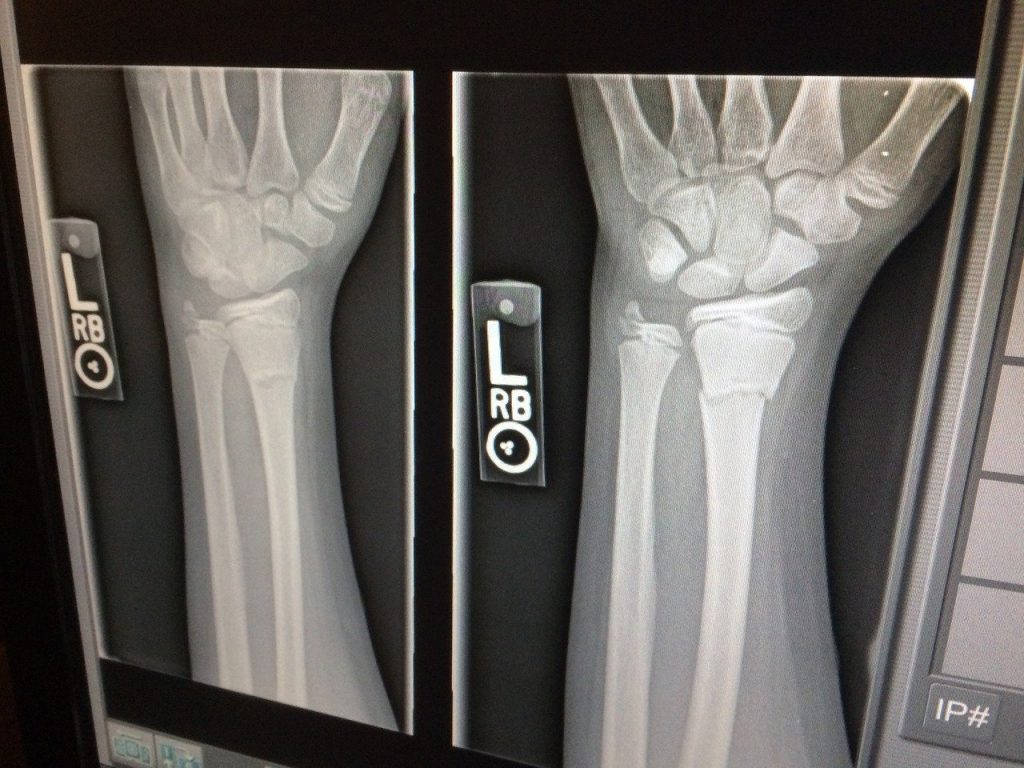

The traditional X-ray, invented way back in 1895, is the oldest form of medical imaging, but it has advanced exponentially since then. Computed Tomography (CT) combines the use of X-ray images and the power of computer processing, enabling CT scanners to take images on 3 different planes, providing a much more detailed picture and enabling a more accurate diagnosis and treatment. The acquisition of the images is vastly sped up using this process.

X-rays are most commonly used to take images of bones and joints to assess the extent of an injury. They are also used to detect any issues with soft tissue, mainly internal organs.